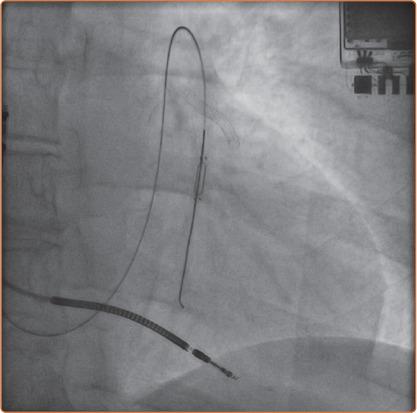

A 57-year-old woman with New York Heart Association Class III heart failure requiring multiple hospitalisations over the previous year presented for CardioMEMS implantation. Because of the patient's allergy history of anaphylaxis to iodine-based contrast agent she underwent the device implantation with gadolinium-based contrast agent (Magnevist), which was successful.

一名57岁女性,纽约心脏协会心功能Ⅲ级心力衰竭,过去一年需多次住院治疗,前来接受CardioMEMS植入。由于该患者对碘造影剂有过敏反应病史,她在植入设备时使用了钆造影剂(马根维显),手术成功。